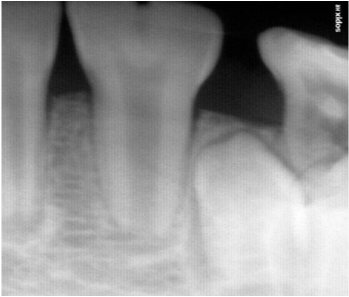

A 10 year old boy reported to the Department of Pedodontics and Preventive Dentistry, Narayana Dental College, Nellore, Andhra Pradesh for routine dental check-up, presented with a large tooth in the lower left front region of the jaw (Figure 1). The boy was not concerned about the aesthetic appearance. The medical and family histories were not significant. Extraoral examination did not show any alterations. Intraoral examination revealed an early mixed dentition period with the presence of one large incisor that was abnormally wide on the left side of the lower arch (Figure 2 and 3). The child had 20 teeth and normal eruption pattern and occlusal status was evident. The double tooth presented a groove upto the cervical third of the crown and hypoplasia on the labial surface (Figure 4). Periapical radiograph displayed the connated incisor with a single root and single pulp canal (Figure 5). The orthopantomograph revealed the presence of double tooth along with the absence of lower left lateral incisor (Figure 6).

Figure 4 Periapical radiograph showed that the connated incisor had a single root and single pulp canal and absence of permanent lateral incisor tooth bud.